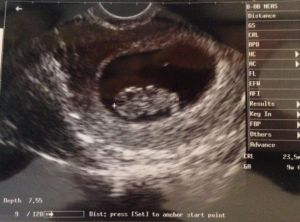

We had our first prenatal appointment yesterday at exactly 9 weeks, and we got to see our baby again! This time, he/she looked much more like a baby… or at least like a gummy bear. He/she was wiggling arms and legs, and the heart was beating like crazy. It actually made me tear up, seeing the baby move – the first time I’ve actually gotten emotional this pregnancy. I think it’s finally starting to feel real, and now that we’ve had two scans and I’ve reached 9 weeks, I’m starting to think we may actually get to take this baby home. We’re still not in the clear for about 3 more weeks — and really, even then there are no guarantees — but like I said, it’s definitely feeling more real. D even said he’ll probably tell his mom, so I know he’s finally getting excited too.

IMG_5829

Baby: We have officially reached fetus status, as baby is no longer an embryo! Baby is about the size of a green olive (is it bad I’m craving green olives?), and is developing more distinct facial features this week.